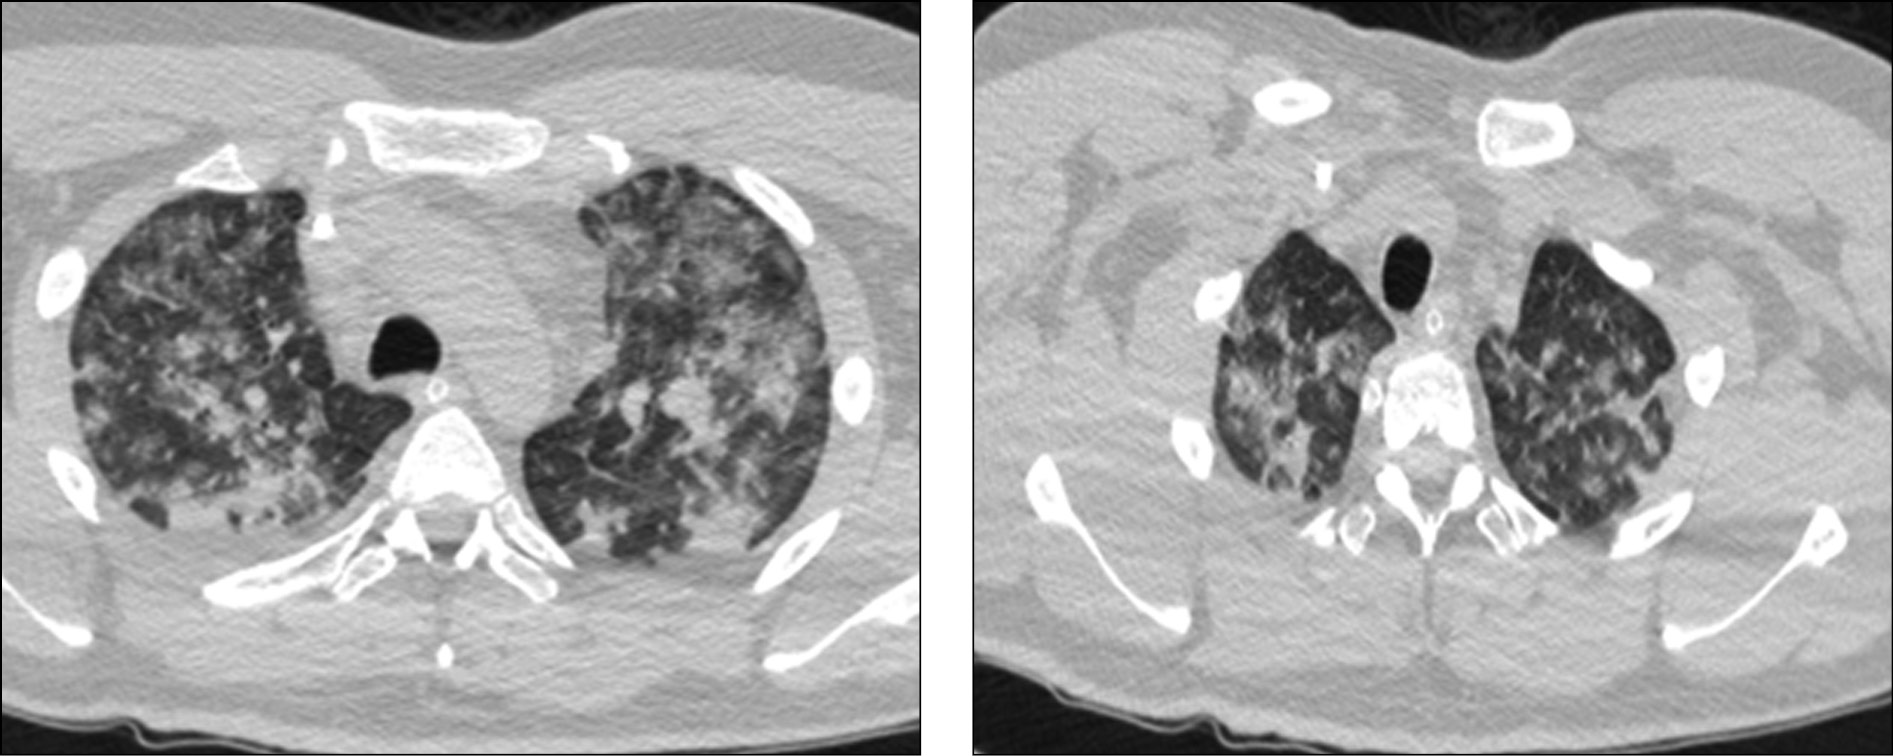

По данным КТ легких, на фоне улучшения состояния легочной ткани отмечалось развитие правосторонней нижнедолевой бронхопневмонии (рис. 2).

Рис. 2. Компьютерная томография легких от 29.04.2020: на фоне улучшения состояния легочной ткани отмечается развитие правосторонней нижнедолевой бронхопневмонии